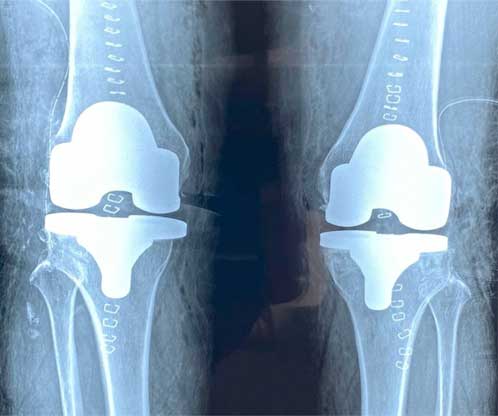

También conocida como artroplastia de rodilla, es la sustitución artificial de la articulación desgastada por artrosis con un implante de metal y polietileno que ayuda a aliviar el dolor y restaurar la función.

La razón más frecuente es aliviar el dolor intenso causado por artrosis, corregir las deformidades angulares en varo, valgo y contractura en flexión en adultos mayores y para adultos jóvenes, está indicada en lesiones crónicas articulares que ocasionan un desgaste acelerado.

El paciente puede caminar desde el mismo día de la cirugía, se da de alta a su domicilio a las 24 horas, realiza actividades cotidianas en casa de forma autónoma desde la primera semana, recupera el 80% de la función de la rodilla al primer mes, 90% de la función en el segundo mes y 92% - 98% de la función en el tercer mes.

Eliminar el dolor en la zona afectada, mejorar la función como es fuerza muscular, movimiento, estabilidad, biomecánica, logrando mejorar la calidad de vida del paciente.

Radiografia AP de ambas rodillas donde se observa deformidad en valgo de rodilla derecha

Foto clínica antes de iniciar una cirugía de reemplazo total de rodilla,